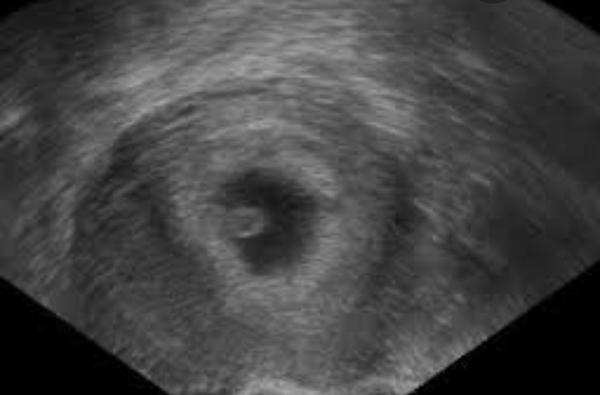

Pro představu přidávám ultrazvuk z internetu, vypadalo to zhruba takhle.. Svoji fotku bohužel nemám.